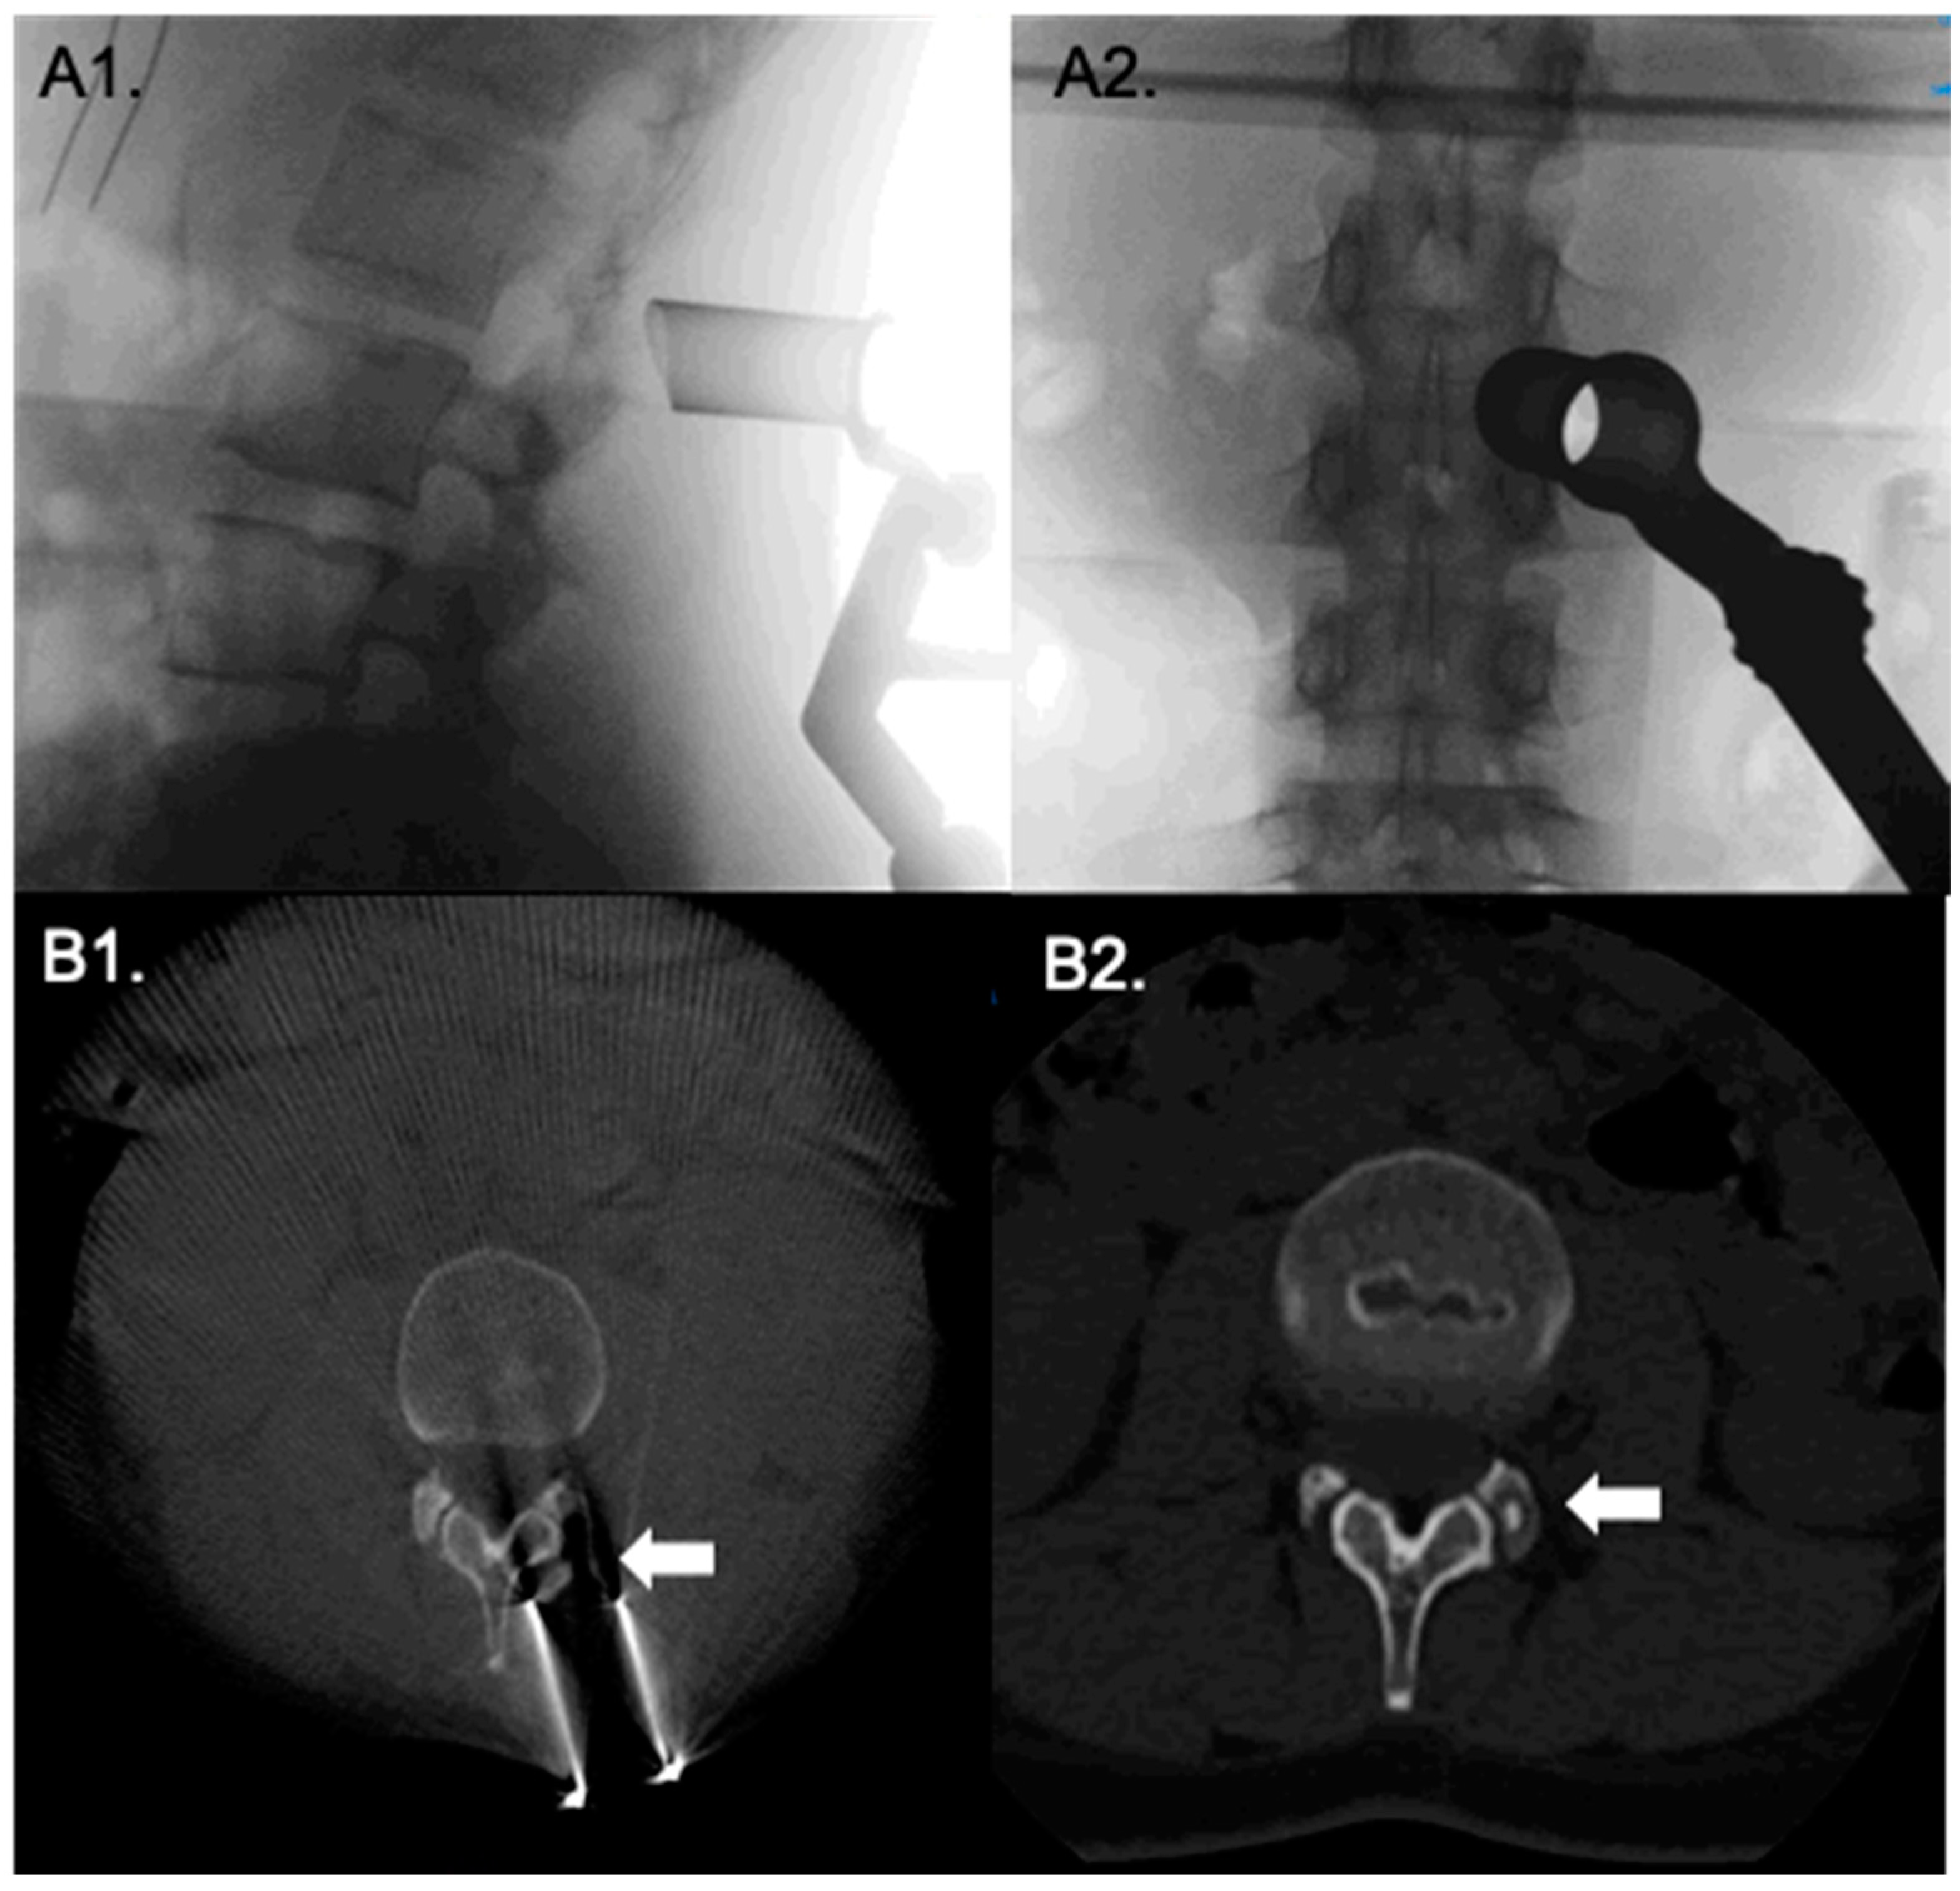

Surgical Technique